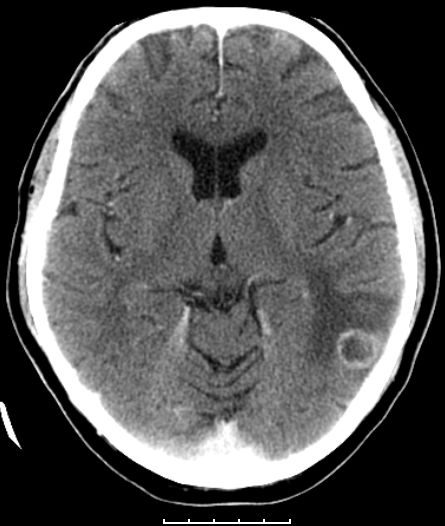

Häufige Metastasierung ins Gehirn. Auch Knochen, Leber, Nebennieren.

Kleinzelliges Bronchialkarzinom des rechten Hauptbronchus T4 N2 M1bra.